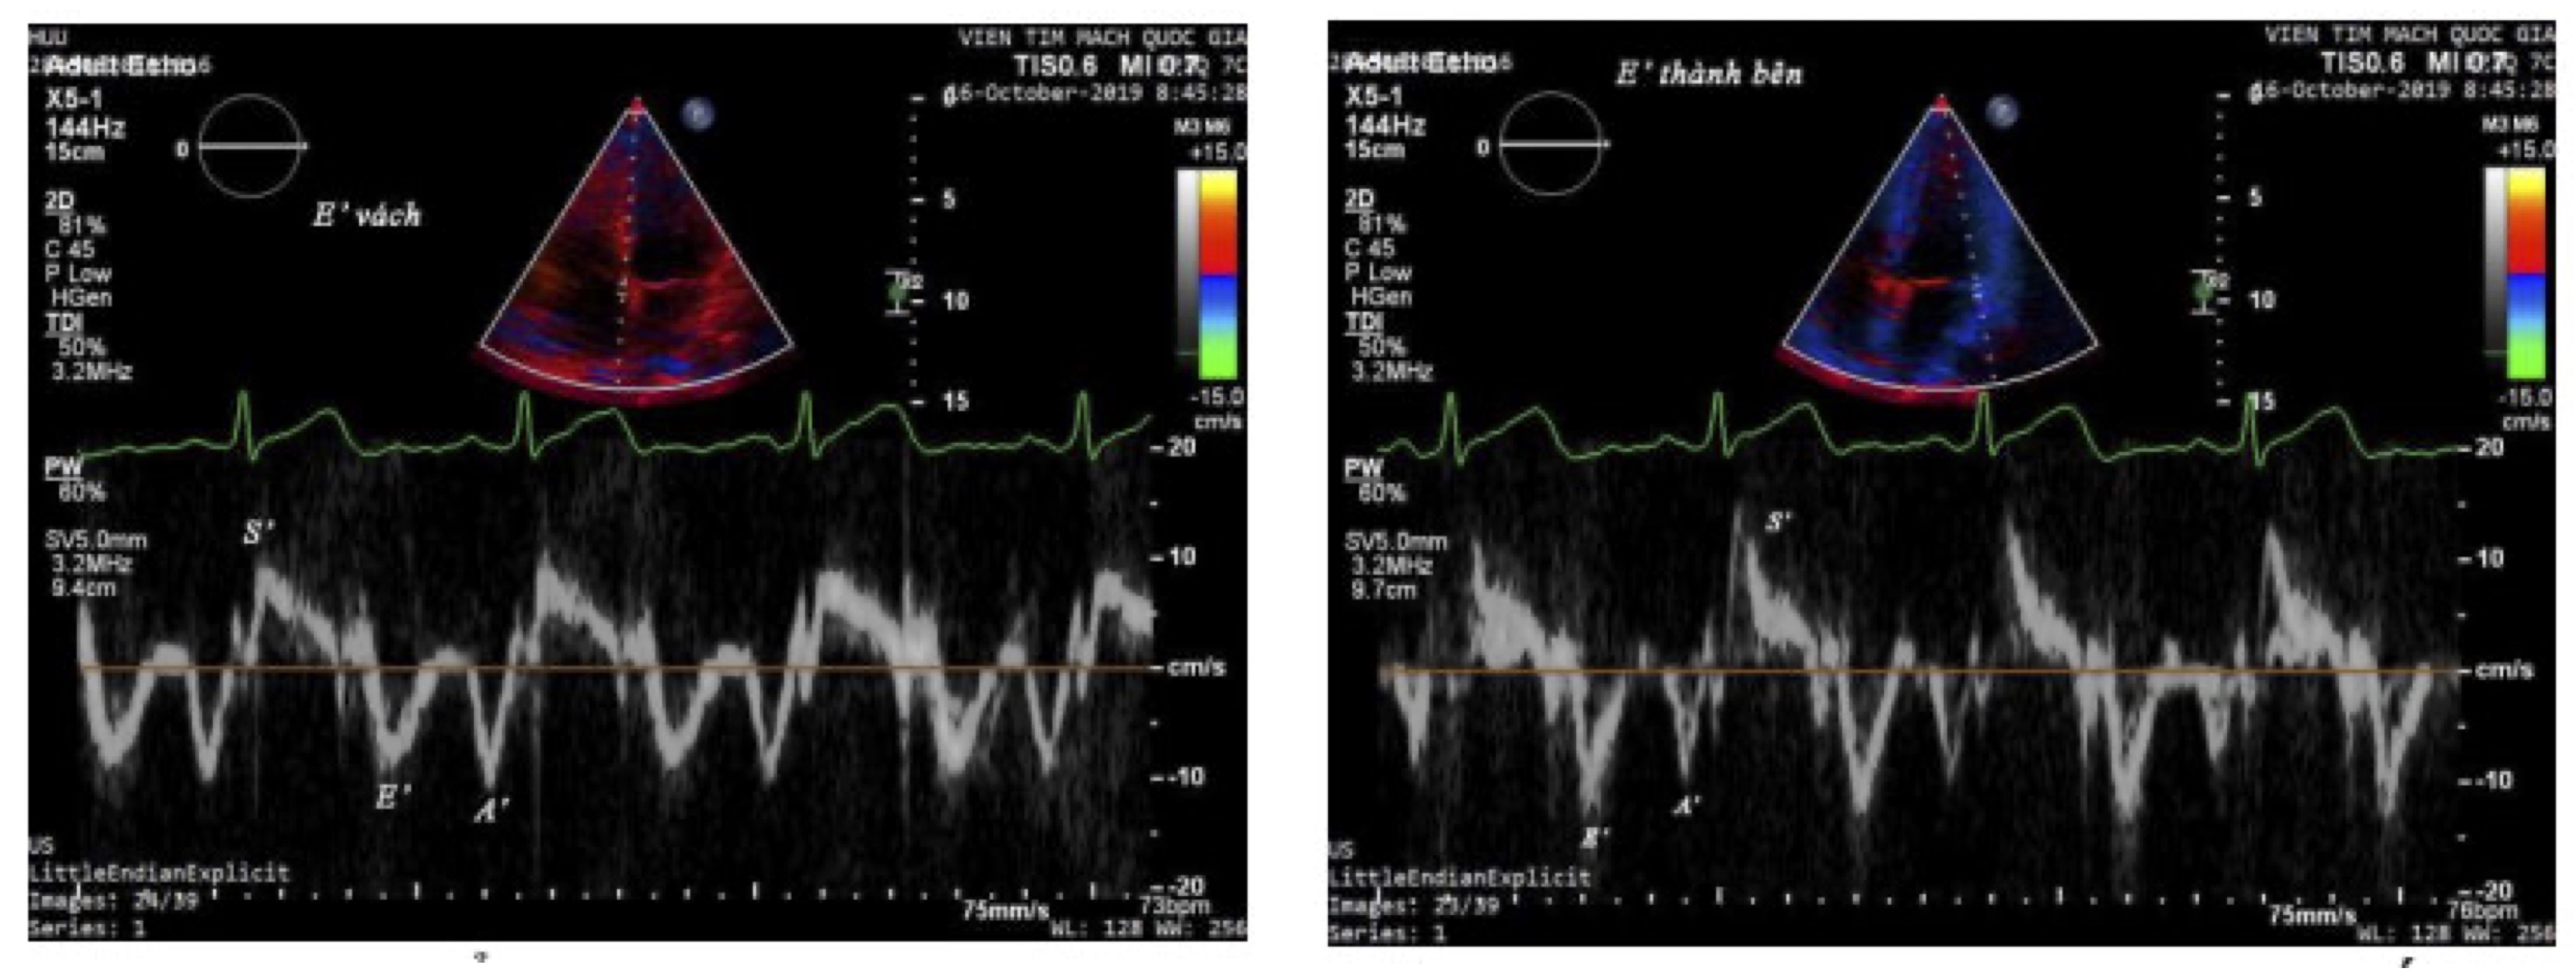

The Cardiac Doppler ultrasound was performed on all selected patients participating in the study using a JIS6 ultrasound machine at the cardiac ultrasound room of the Vietnam National Heart Institute. The measured results were assessed by a group including cardiac ultrasound specialists at the cardiac ultrasound department of the Vietnam National Heart Institute. Ultrasound parameters were measured and calculated according to the guidelines of the American Society of Echocardiography (2008) on an ultrasound machine with Tissue Doppler and myocardial tissue tagging functions, using the JIS6 ultrasound machine.4 The ultrasound parameters were examined in the following sequence (Fig. 1).

...

Fig. 1: Doppler ultrasound image of myocardial tissue

Tissue Doppler Echocardiography

Measured from the apical four-chamber view with the Tissue software available on the ultrasound machine. The Doppler sample volume was placed at the basal interventricular septum using the TDI software, measuring the velocity of e', a', and s' waves. The Doppler sample volume was placed at the basal lateral wall of the left ventricle using the TDI software, measuring the velocity of e', a', and s' waves.